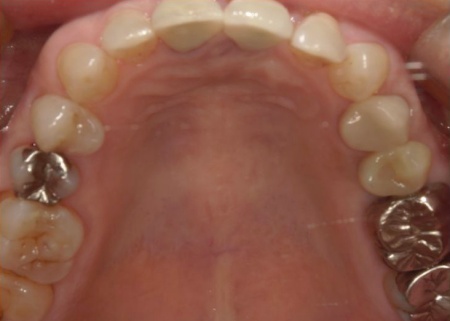

70代女性 歯根が折れた左上奥歯を抜いてインプラント治療で噛み合わせを回復した症例

インプラントが顎の骨と結合したあと、人工歯を装着します。

また、手前の歯にも新しい被せ物を装着しました。

最後に、見た目や噛み合わせに問題がないことを確認し、治療を終了しています。